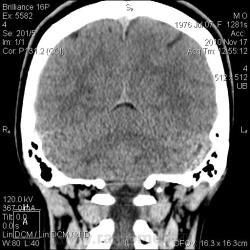

Тип патологии:

Область исследования:

Методы исследования:

- https://radiomed.ru/sites/default/files/styles/case_slider_image/public/user/2841/arnolda-kiari_1_st0003.jpg?itok=RhH96K1Y